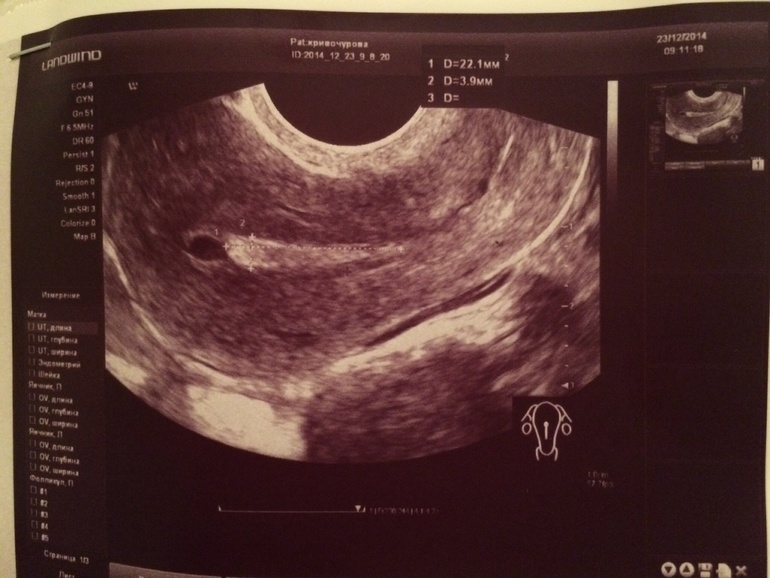

Добрый вечер!полип эндометрия,а обнаружен УЗИ.я бы приложила фото узи,только я не знаю как это с телефона сделать?!

УЗ-признаки полипа эндометрия. В подобных случаях требуется дополнительное обследование- оценка эндометрия при помощи гистероскопа ( офисная гистероскопия). Если полип подтвердится во время исследования врач сможет решить вопрос о возможности перехода на режим удаления полипа при помощи эндоскопического инструмента, или же произвести раздельное диагностическое выскабливание. Лучше решить эту проблему до планирования беременности, так как локализация полипа может помешать наступлению беременности.

По данным УЗИ имеются признаки полипа эндометрия, но УЗИ не позволят точно выставить диагноз, тем более касающийся новообразований. Поэтому требуется метод диагностики, основанный на непосредственной визуализации полости матки- это гистероскопия. Часто этот метод используют в как начальный этап удаления полипа — то есть при помощи гистероскопа увидели полип, далее приступают к его удалению. Крайне редко, когда в мед учреждении нет гистероскопа приходится выполнять выскабливание стенок полости матки без визуализации их, а далее по результатам гистологии судят о том, какое было образование.